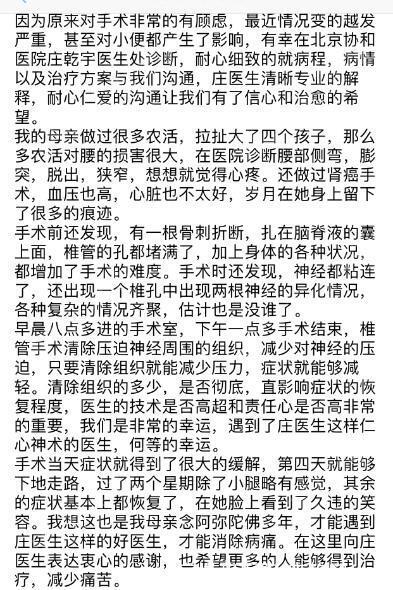

患者手术过程顺利,完全按照手术方案完成。通过一次手术解决了患者的腰椎管狭窄、腰椎侧弯和腰椎滑脱;虽然患者存在韧带骨化,硬膜压迫明显,但通过精细操作未出现脑脊液漏;术后患者腰痛及间歇性跛行的症状明显缓解,侧弯导致的外观异常和躯干偏移也明显矫正;术后X片可见腰椎侧弯及腰椎滑脱均得到满意的矫正。